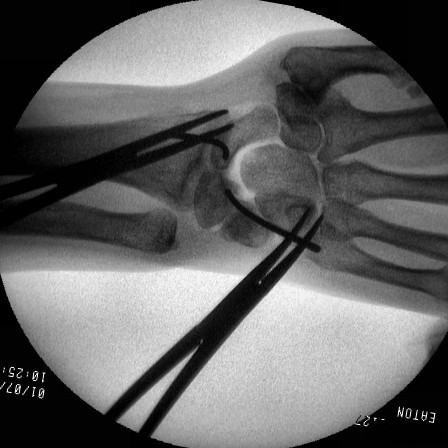

In this case, the scapholunate repair was stabilized with absorbable (Bionx) screws. Provisional fixation for two screws with a pin and a drill.

Click for larger image

These were then replaced with screws, which are radiolucent.

Lucency where a screw lies.